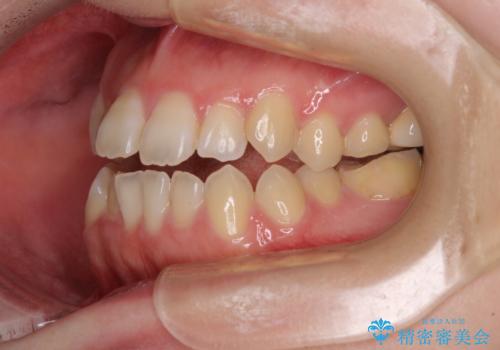

オープンバイトと前歯のデコボコをインビザライン矯正で解消

オープンバイトは舌の突出癖により誘発され、治療後も突出癖が残っている容易に後戻りしてしまいます。

治療期間を短縮するためにも、舌突出癖の改善が極めて重要となります。